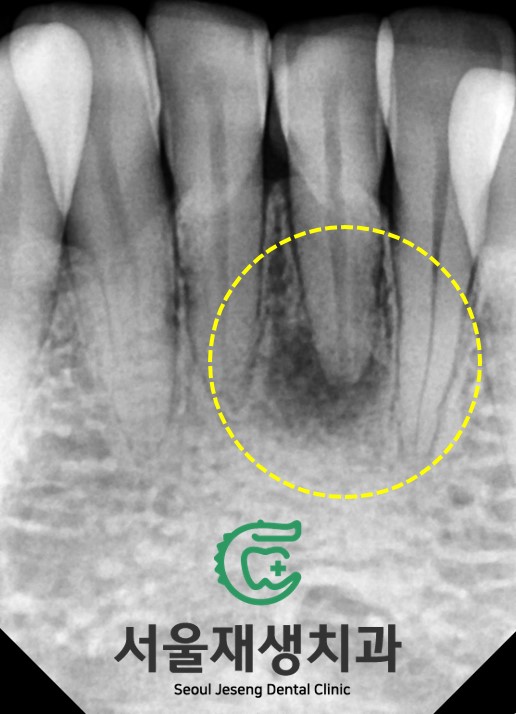

출처 아카이브 열기![[치아미백] 예전에 부딪힌 앞니가 까맣게 변했어요. 신경이 죽은 치아를 하얗게 돌려놓기! (서울재생치과) 관련 이미지 1](https://pub-9f2bb3498faf4d1d8714b41df24753e3.r2.dev/content/clinics/archive/nqmm0udu86/naver_blog/honeybeevuvu/assets/by_hash/36a6653b0482bc9102c40ee67ed182c160e6114fc205eb0d5391b46a41debf62.jpg)

예전에 아래 앞니를

심하게 부딪힌 적 있어요.

지금 아프진 않아요.

![[치아미백] 예전에 부딪힌 앞니가 까맣게 변했어요. 신경이 죽은 치아를 하얗게 돌려놓기! (서울재생치과) 관련 이미지 2](https://pub-9f2bb3498faf4d1d8714b41df24753e3.r2.dev/content/clinics/archive/nqmm0udu86/naver_blog/honeybeevuvu/assets/by_hash/68674c62217a6d123c0e62846e51fd0a2e9b1fd0932c7c8a1cb2f7bc6585ed59.jpg)

약간의 부정교합이 있지만

보기 좋은 치아 배열입니다.

앞니 아래로 숨은

작은 아래 앞니가

조금 어두워보이는데...

다들 찾으셨나요?

![[치아미백] 예전에 부딪힌 앞니가 까맣게 변했어요. 신경이 죽은 치아를 하얗게 돌려놓기! (서울재생치과) 관련 이미지 4](https://pub-9f2bb3498faf4d1d8714b41df24753e3.r2.dev/content/clinics/archive/nqmm0udu86/naver_blog/honeybeevuvu/assets/by_hash/2af6f4edd10f764de6ac06a6947816f68b868c5641db493ef9ee4554442d78b7.jpg)

원인은

치아신경의 괴사!!

아주 옛날에 겪은 부딪힘 사고로

치아 내의 신경이 수년에 걸쳐

서서히 죽을 수 있다는 사실,

알고 계셨나요?

신경치료를 먼저 시행해줍니다.

![[치아미백] 예전에 부딪힌 앞니가 까맣게 변했어요. 신경이 죽은 치아를 하얗게 돌려놓기! (서울재생치과) 관련 이미지 6](https://pub-9f2bb3498faf4d1d8714b41df24753e3.r2.dev/content/clinics/archive/nqmm0udu86/naver_blog/honeybeevuvu/assets/by_hash/664d8bf8646daf1cf433dfa0e763677509ff56396f15e0b979f34ef27d097aec.jpg)

뿌리 내에 있는 오염된 조직들을 제거하고,

깨끗하게 밀봉해주었습니다.